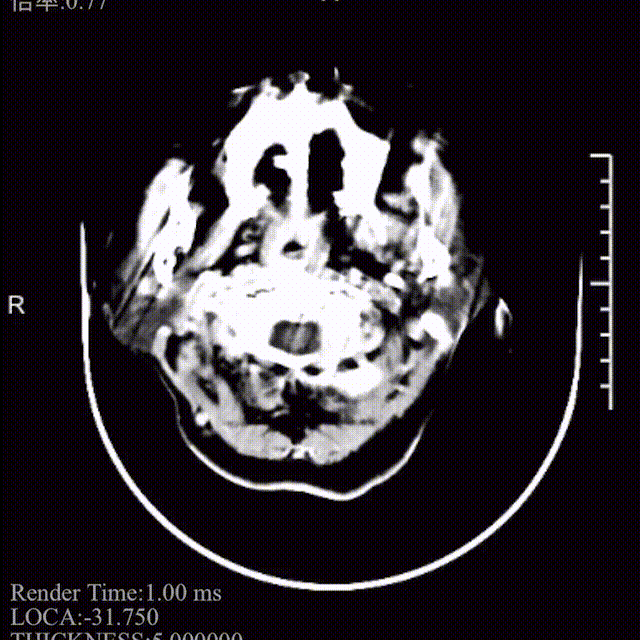

术前影像学检查

左侧丘脑及双侧侧脑室旁白质区可见点片状低密度影,影像诊断左侧丘脑及双侧侧脑室旁白质区腔隙性脑梗塞;老年性脑改变。